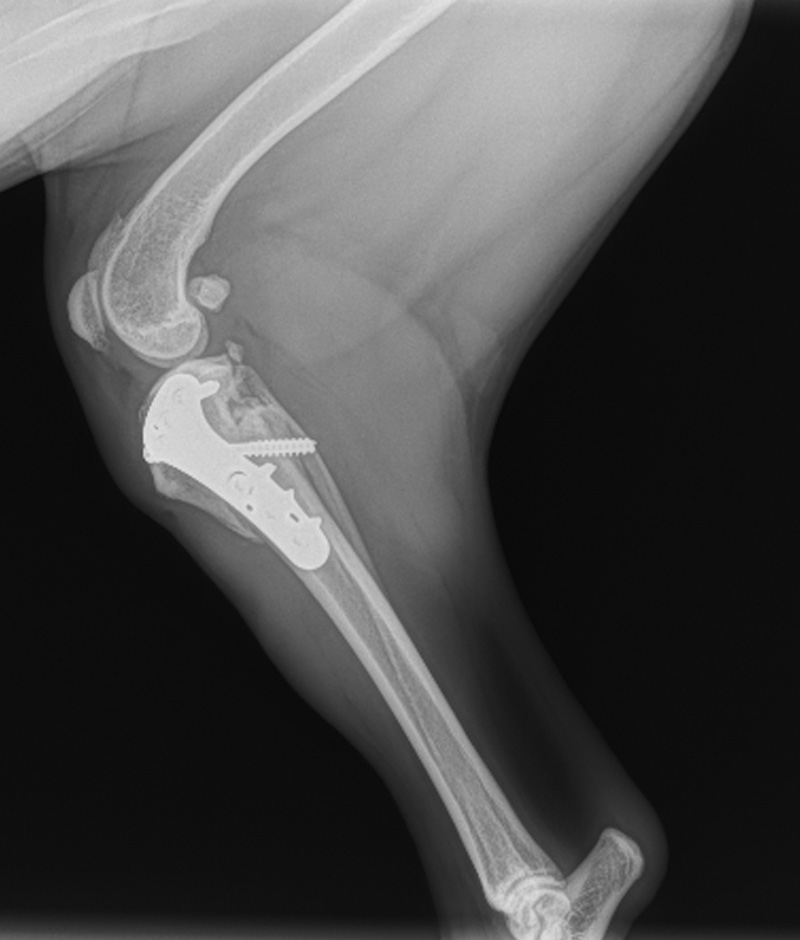

Orthopedic Surgery Services for Animals

Expert Joint and Ligament Repair by a Board-Certified Veterinarian

Our veterinary clinic specializes in advanced orthopedic surgery for animals, focusing on joint and ligament repair. Led by a board-certified surgeon, our surgical team is dedicated to restoring mobility, reducing pain, and improving the quality of life for your pets.

Joint and ligament injuries can significantly impact an animal’s ability to move comfortably. We offer a wide range of surgical interventions, from traditional open repairs to minimally invasive arthroscopic techniques. Our expertise includes repairs for common conditions such as cranial cruciate ligament tears (CCL), patellar luxation, hip dysplasia, fractures and more.